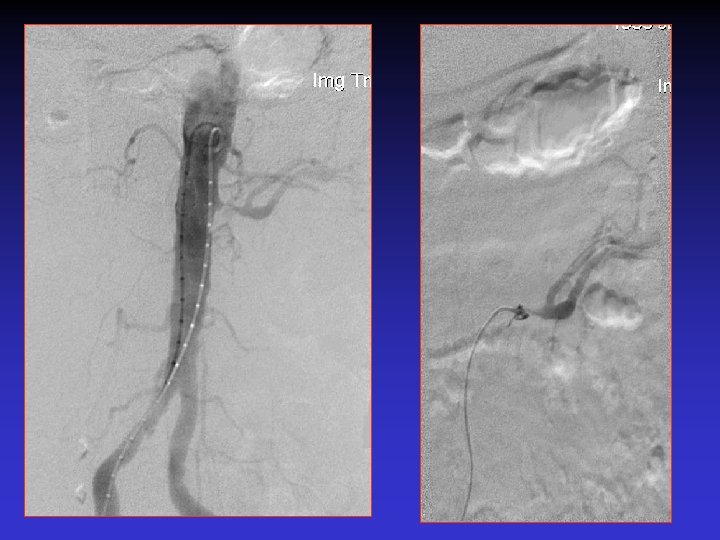

Case # 2 • 50 -year-old male with solitary kidney. • Smoker. • Refractory HTN. • Cr: 3. 8 mg/dl

• B/P: 160/80 mm. Hg • Cr: 1. 8 mg/dl

The patient was re-admitted 18 months later with Cr: 2. 8 mg/dl, and BP: 180/90 mm. Hg.